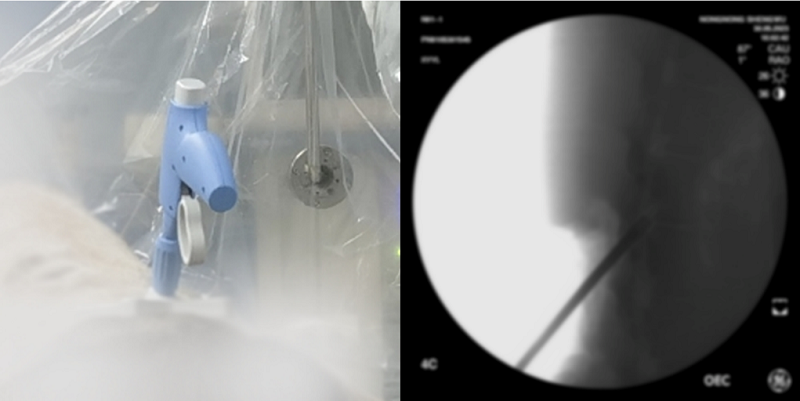

2014年創(chuàng)辦金科君創(chuàng)以來,主導(dǎo)投資了天智航(688277)、漢氏聯(lián)合、快舒爾、先思達、大艾機器人、中航邁特、三帝科技、數(shù)字精準(zhǔn)、瑞爾醫(yī)療、東方瑞豐、博清科技、羅森博特、中科聞歌、真健康、飛諾門陣、中科通量、睿芯IC等眾多優(yōu)秀科技企業(yè)。